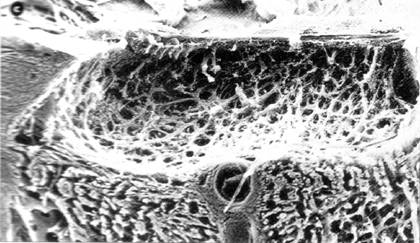

Modificarile papilare apar ca urmare a tulburarilor circulatorii de la acest nivel, consecutive cresterii presiunii oculare si a devierii fluxului sanguin ; ca urmare apare distructia fibrelor gliale de sustinere cu aparitia excavatiei (Fig. 13.6) si distructia fibrelor nervoase, cu aparitia decolorarii papilare (atrofia optica).

Fig 13.6 - Evolutia excavatiei papilare in cursul glaucomului cu unghi deschis

papila nervului optic prezinta excavatie totala, care intereseaza toata suprafata papilara, cu raport C/D = 0.9-1 (Fig.14.9) ; de asemenea papila este decolorata, prezentand atrofie optica.

Fig. 13.9 - Aspectul histologic al papilei optice in stadiul III de glaucom